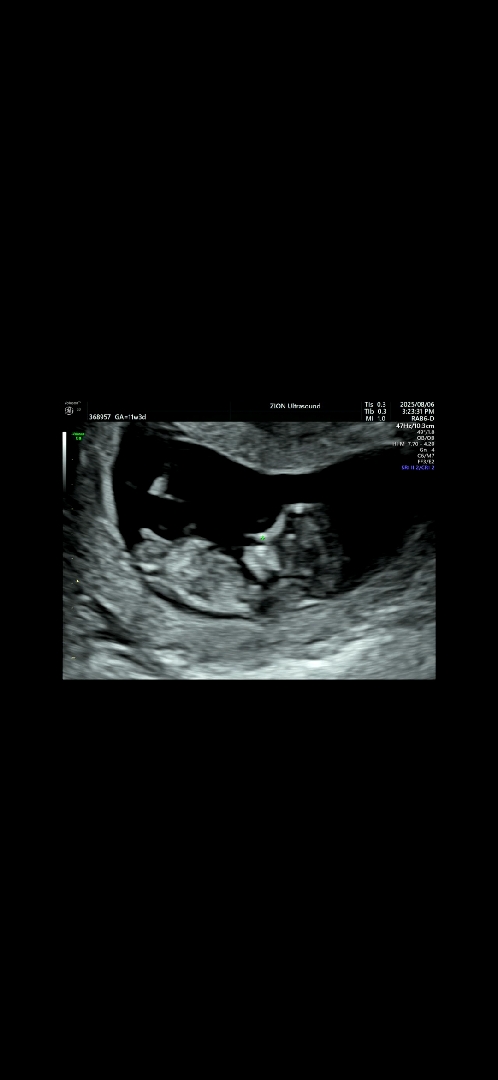

11주3일)각도법 고수님들 알려주세요♡

오늘 1차기형아검사하면서 찍은사진인데, 성별 재미삼아 알려주세요~

아들이용

딸인듯 아들인듯.. 평행한데 존재감이 커보이네요ㅋㅋㅋ